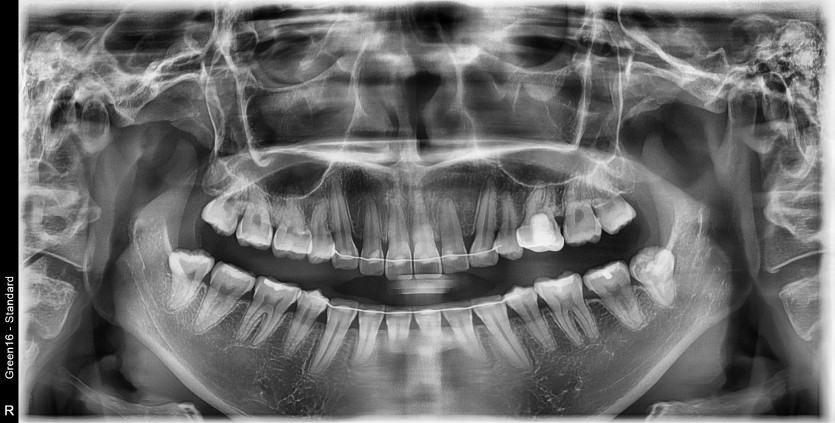

#18,28,38,48 사랑니 발치

구강 외과 전문의가 당일 발치했습니다.